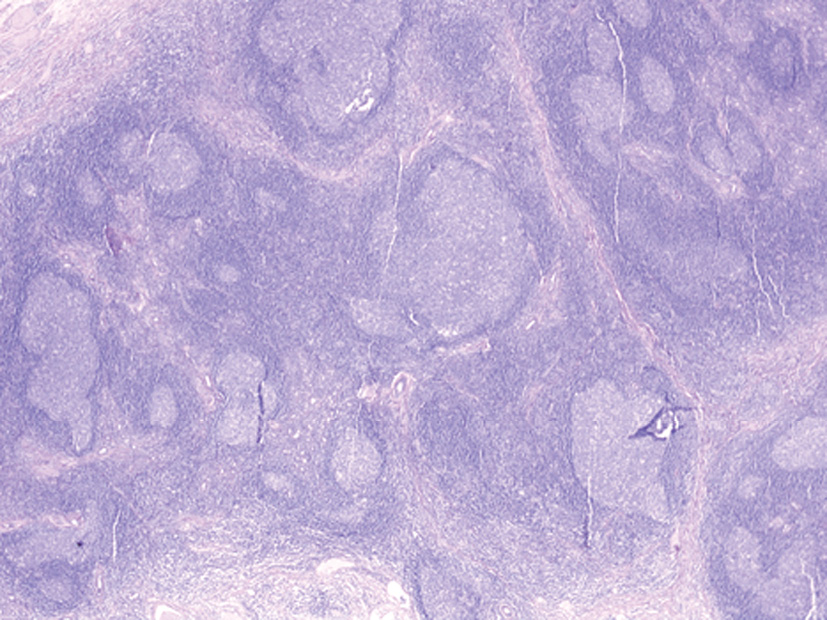

При гистологическом исследовании выявлены фрагменты фиброзной ткани со структурами слезной железы, многочисленными лимфоидными фолликулами с широкими центрами размножения; присутствовали пласты зрелых плазматических клеток, расположенных парафолликулярно, перидуктально, часть из них – интрафолликулярно, с примесью эозинофильных гранулоцитов (рис. 3, 4).

Рис. 3. Лимфоидная инфильтрация ткани слезной железы представлена многочисленными вторичными фолликулами.

Окраска гематоксилином и эозином (ув. ×25).

Рис. 3. Лимфоидная инфильтрация ткани слезной железы представлена многочисленными вторичными фолликулами. Окраска гематоксилином и эозином (ув. ×25). Доступен на цветной вклейке и в сети Интернет: https://doi.org/10.14341/probl10223-4022 |

|